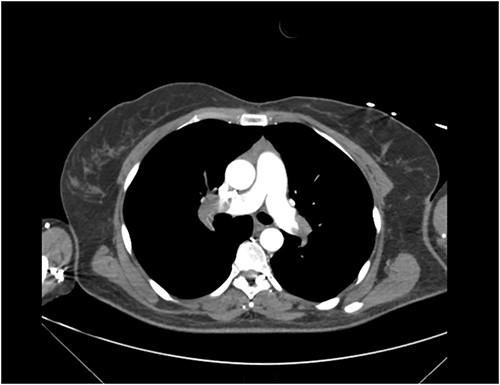

Clinical examination revealed a middle-aged female in respiratory distress. Vitals on triage were blood pressure of 146/103 mmHg, pulse rate of 110 beats per minute, respiratory rate of 31 beats per minute and saturation of 67% on oxygen at 15 L/min. Well’s score was calculated at 6.0. CT pulmonary angiogram revealed extensive PE with filling defects in the right and left pulmonary arteries extending into the right lobar and segmental arteries, left upper segmental and lingula branches (Fig. 1). A bedside echocardiogram revealed evidence of right heart strain.

CT Pulmonary Angiogram demonstrating filling defects in the left and right pulmonary arteries.